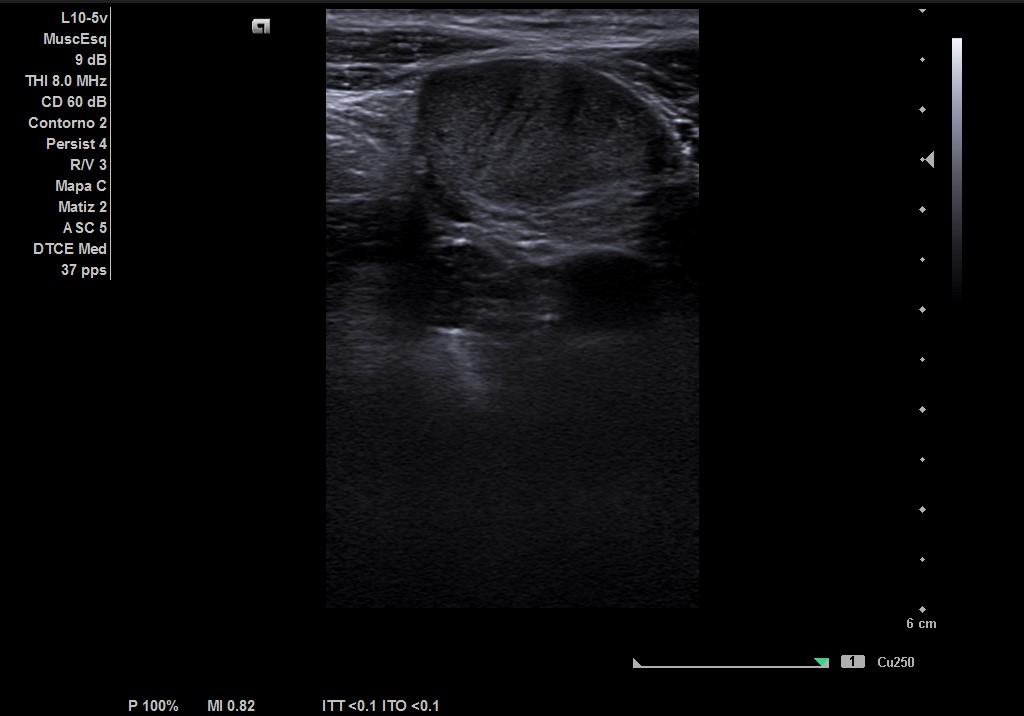

Durante la realización de la prueba, el paciente comenta que en ocasiones no encuentra el testículo derecho. Por lo que decidimos cambiar a la sonda lineal y explorar planos más superficiales donde observamos el testículo derecho, por encima del ligamento inguinal, en fosa ilíaca derecha con ecoestructura normal, homogénea y vascularización normal.